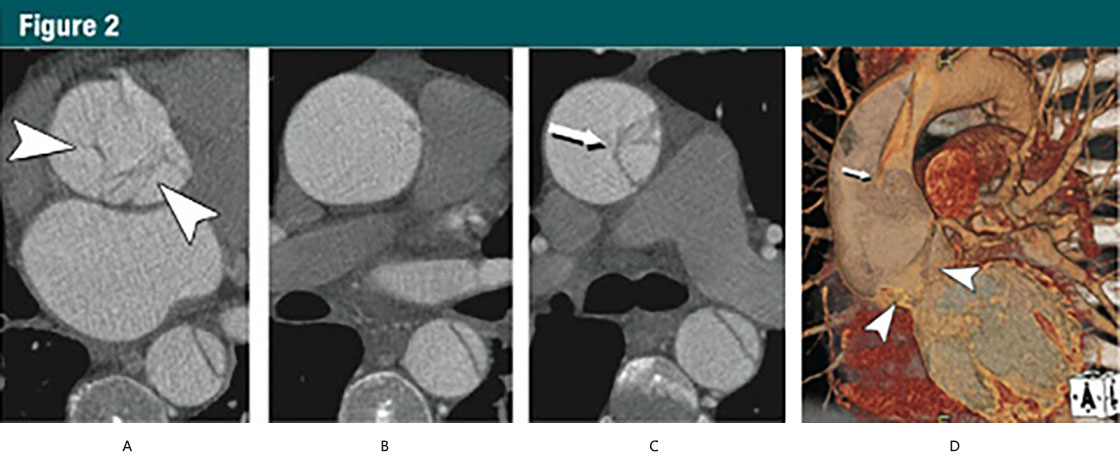

圖2 45歲,男,A型急性主動(dòng)脈夾層

(A-C)CT橫斷位圖像:

(A)主動(dòng)脈根部水平不規(guī)則線樣陰影(箭頭)

(B)升主動(dòng)脈中段沒有夾層皮瓣

(C)升主動(dòng)脈遠(yuǎn)端可見夾在真、假腔之間的夾層皮瓣(細(xì)箭)

(D)VR重建展示夾層,近端夾層撕裂皮瓣下垂向下通過主動(dòng)脈瓣膜(箭頭)。細(xì)箭所指遠(yuǎn)端升主動(dòng)脈的夾層皮瓣。在無ECG門控的時(shí)候,這些細(xì)微的發(fā)現(xiàn)并不可見。(轉(zhuǎn)載、許可、引用30)

Group 1 lesions representing aortic dissection and its variants share a diseased aorticmedia as their common pathologic lesion. Classic dissection is characterized by the development of a flow channel or false lumen within the aortic wall, which is separated from the true lumen by a dissection membrane (Fig2).